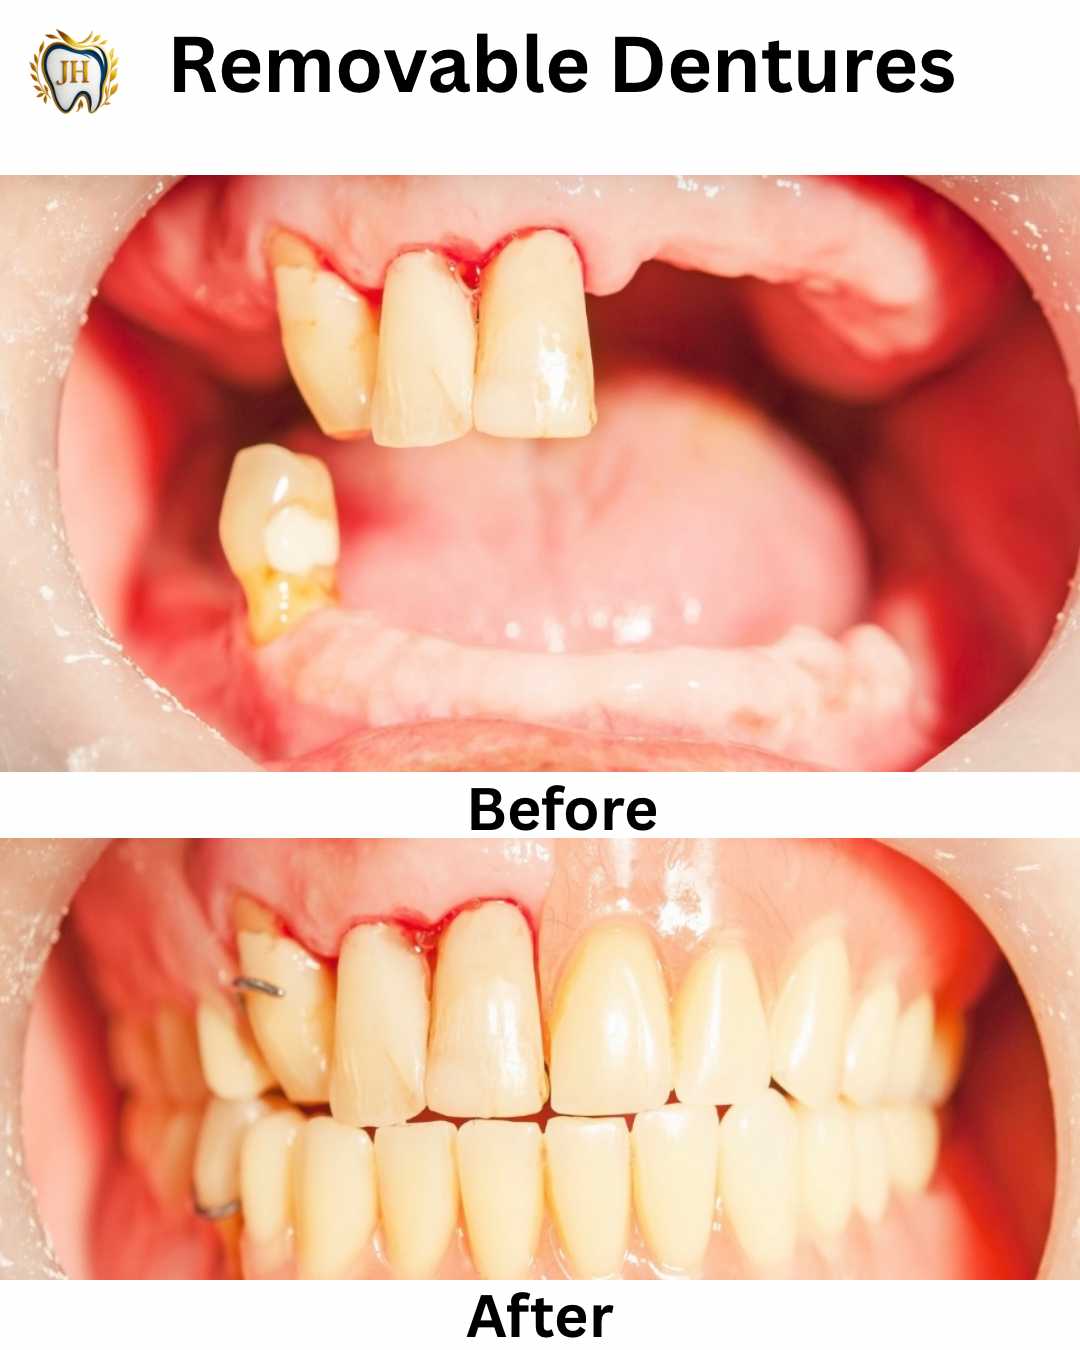

- Dentures (Removable & Flexible)

- Transformations